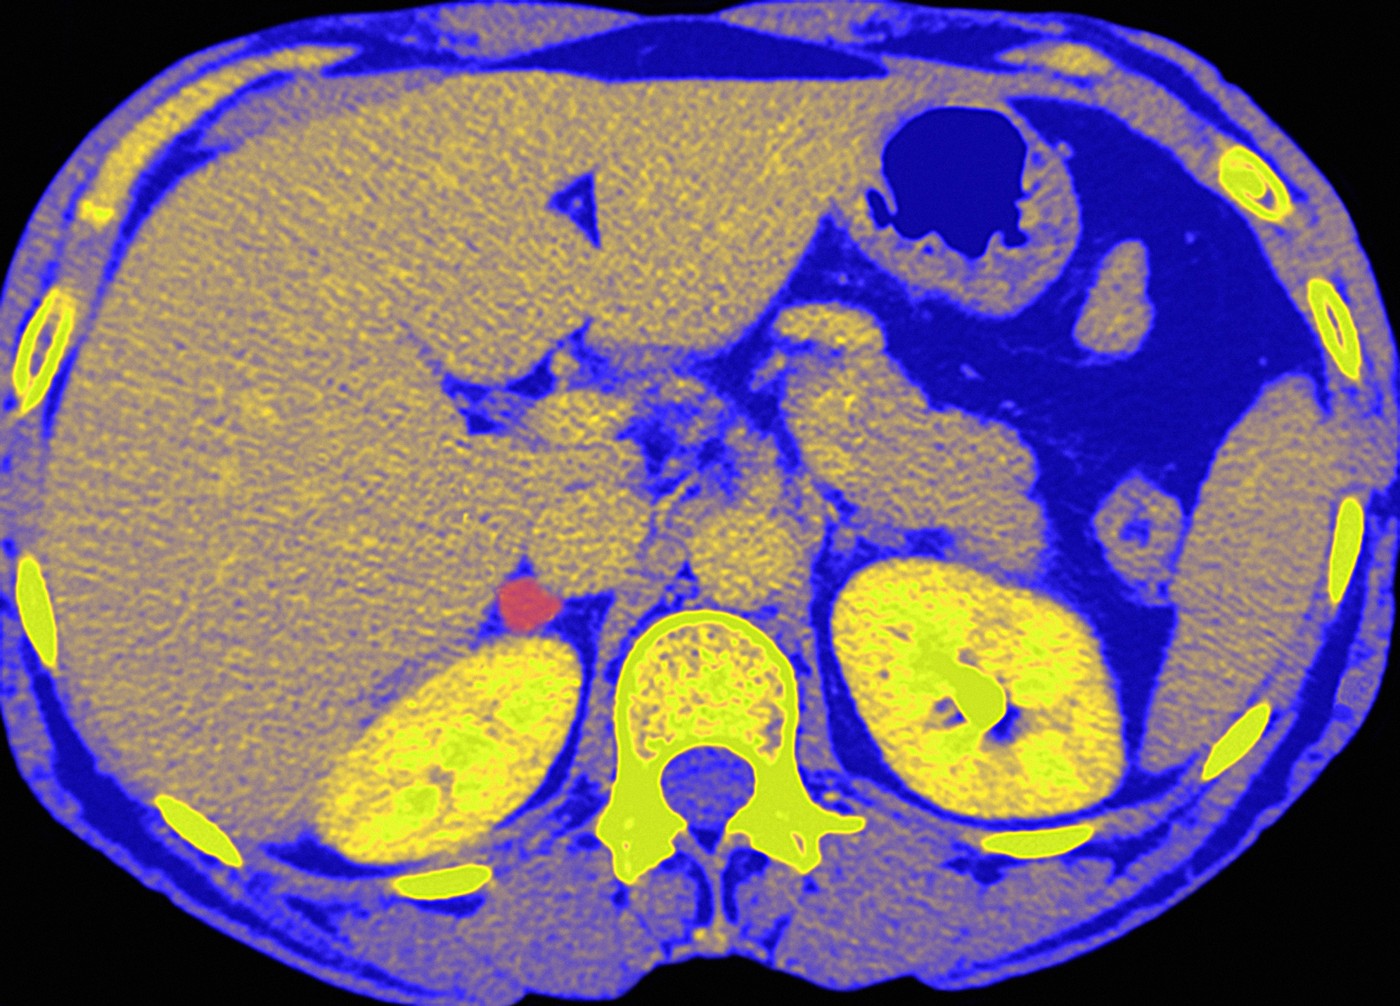

Tumori nadbubrežnih žlezda

Nadbubrežne žlezde se nalaze iznad bubrega. Tumori nadbubrežnih žlezda mogu biti benigni (nekancerogeni) ili maligni (kancerogeni), a mogu lučiti visoke nivoe hormona, uključujući kortizol. Veći tumori mogu pritiskati okolne organe i izazvati osećaj bola ili punoće u stomaku.

Benigni tumori nadbubrežnih žlezda se otkriju kod otprilike 1 od 10 osoba koje se podvrgnu snimanju ovih žlezda. Maligni tumori su znatno ređi.